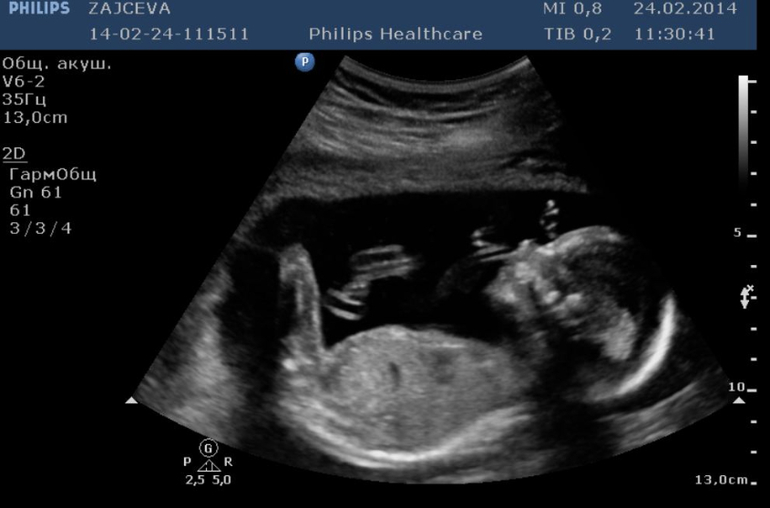

Прекрасные фоточки, мой тоже в прошлом году УЗИ начинал с демонстрации *я мальчик!*